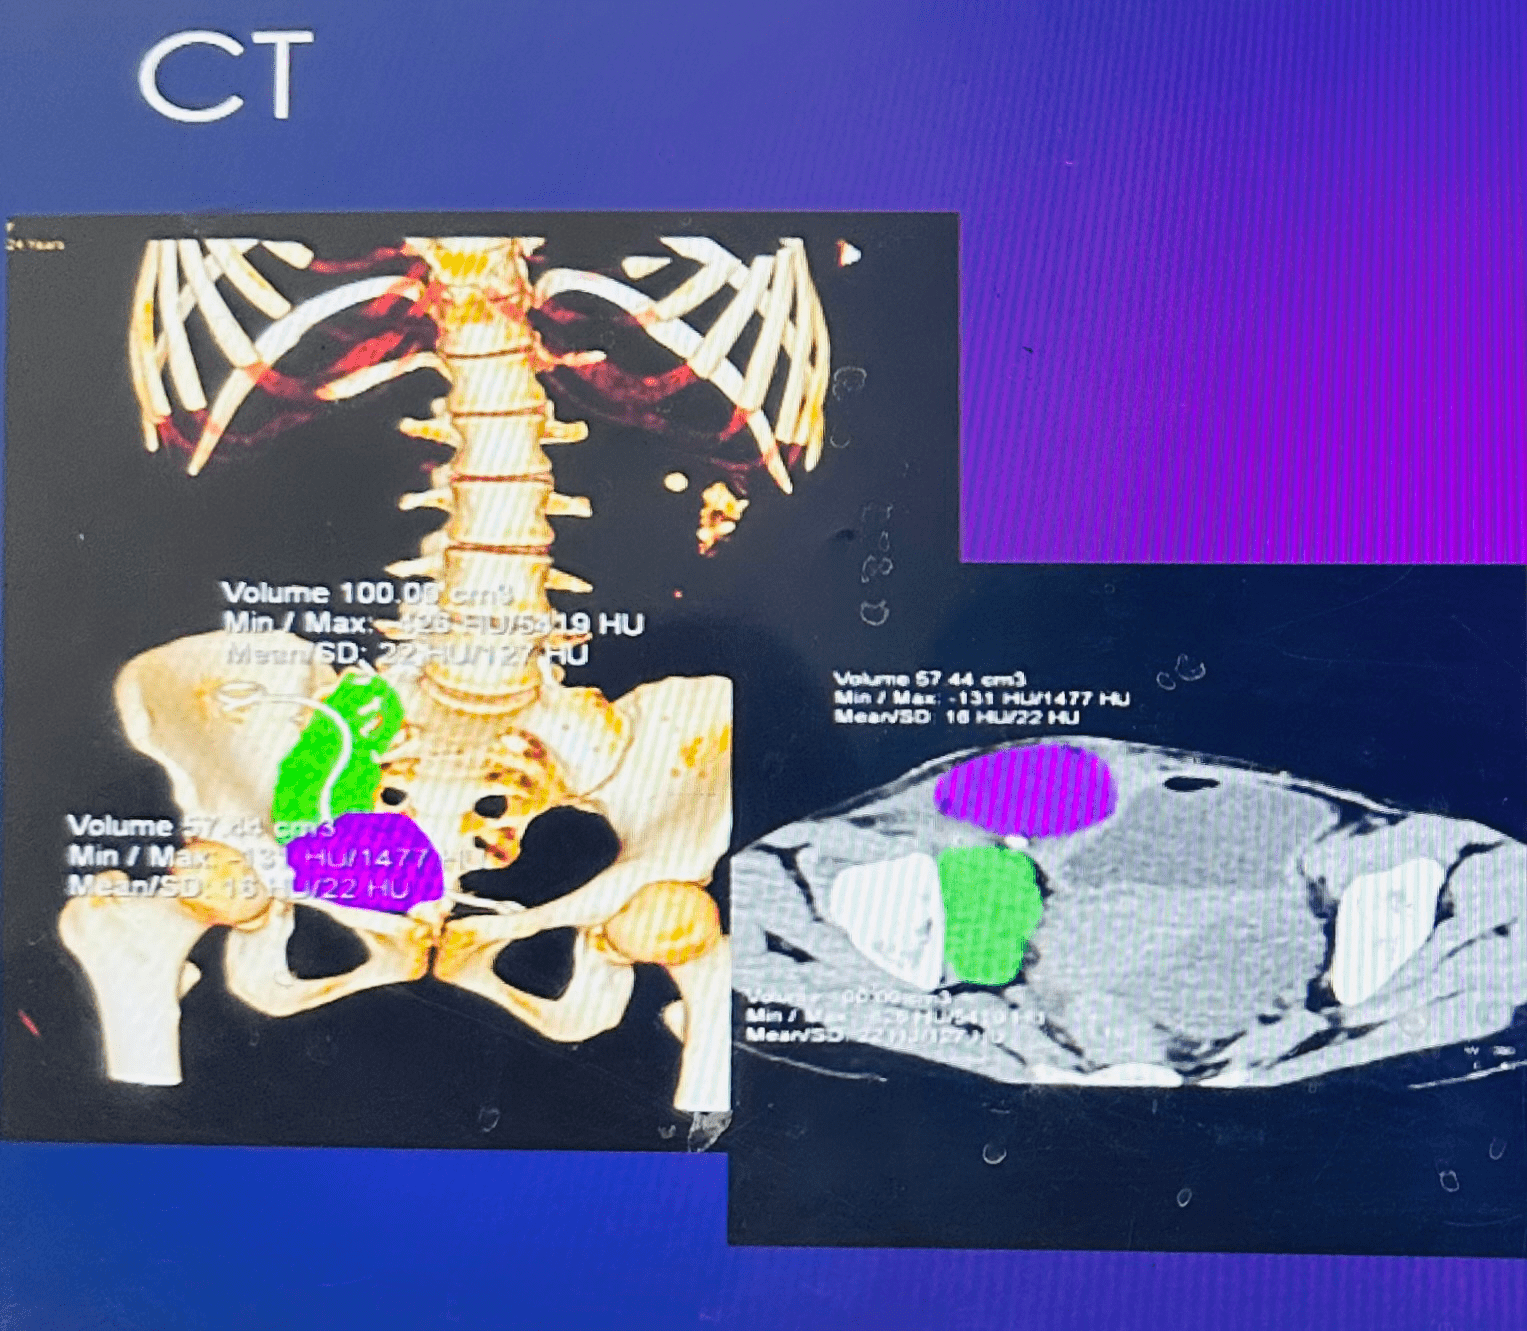

24 year female 3 weeks post renal transplant developed mild graft dysfunction and low grade fever. Imaging showed a large collection abutting the transplant ureter both anteriorly and posteriorly, pig tail insertion was done. Drain output was more than 3 litres per day.

53 year old male 15 days post renal transplant presented with graft dysfunction. USG revealed collection near lower pole of the kidney with mild hydroureteronephrosis. Drain output was 110 ml.

All 3 cases were treated with 20 mg of intra muscular octreotide. There was significant decrease in drain output with radiological shrinkage in the size and there was no recurrence of lymphocele on follow up.